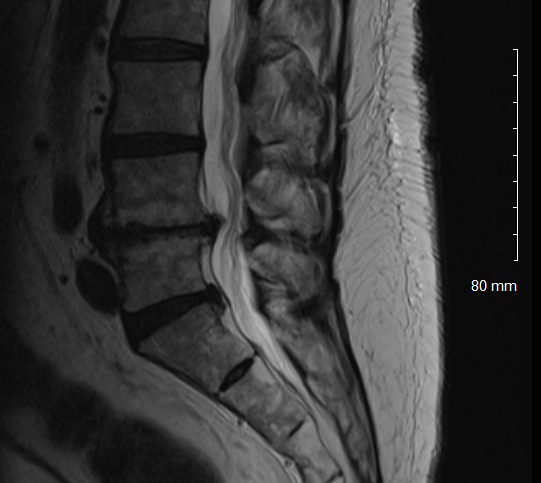

Physical examination revealed hypertonicity and tenderness in the lumbar paraspinal muscles and the left posterior hip region. He reported a pain level of 8/10 on the NPRS, reflecting both LBP and radicular symptoms. Additionally, a score of 32 out of 40 on the DVPRS indicated substantial pain-related functional impairment. A 2024 lumbar spine MRI demonstrated degenerative disc disease, arthropathy, severe left subarticular recess stenosis at L4-L5 with L5 nerve impingement, and a small left central disc extrusion at L5-S1 abutting the S1 nerve root (Figs. 1–4).

This case report documents an unexpected improvement in PLP during chiropractic treatment for LBP and radicular symptoms in a patient with a below-knee amputation. The temporary abolition of PLP reported at Visit 5, which was sustained for 2 weeks, suggests that automated lumbar long-axis distraction and myofascial release may influence the neuropathic pain pathways in amputee patients. Furthermore, lumbar distraction may reduce mechanical compression on the L5 nerve root, as seen on MRI (Figs. 1-4), potentially decreasing spinal cord hyperexcitability associated with PLP.15 Myofascial release, by addressing trigger points and muscle tension, may alter afferent input to the spinal cord, influencing pain processing.16 Chiropractic manipulation has been shown to modulate pain perception and widespread pressure sensitivity, likely through activation of descending inhibitory pathways. While these mechanisms may play a role in conditions involving central sensitization, their relevance to neuropathic pain such as PLP needs further investigation.17